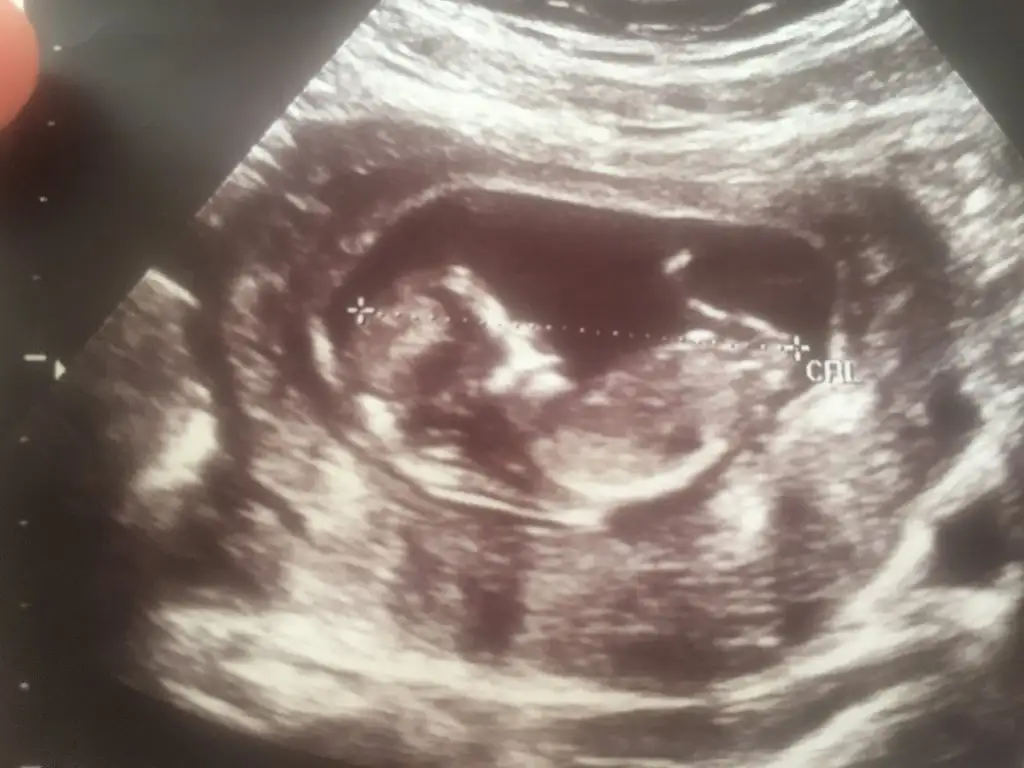

T Takitoki Benim bebeğim 8 haftalık vanija dan bakıldı sağda bebeğim cinsiyeti nedir ☺️

6+5 ve 7+6 acaba nedir çok merak ettim 🥰 T Takitoki